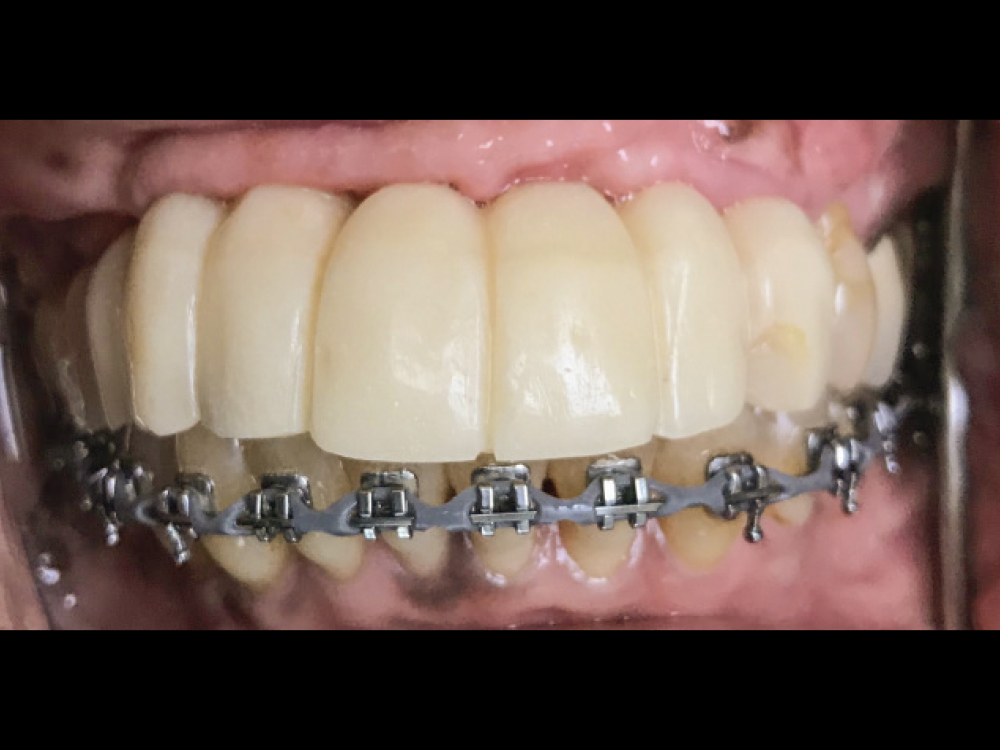

3 months after implant placement, screw-retained provisional implant prosthesis were added

Figure 4: Three months after implant placement, the patient returned, and a screw-retained provisional implant prosthesis was fabricated chairside using non-engaging abutments, flowable acrylic, a vacuum thermoforming machine and the patient’s existing partial denture as a template. Orthodontic treatment was undertaken for the lower arch to intrude the supererupted mandibular teeth and level the occlusal plane.